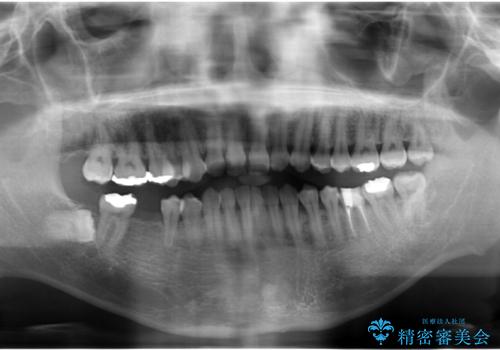

- 右下の奥歯にインプラントを入れたいと来院。

抜歯から時間が経っており、骨が十分あったためすぐにインプラントを入れることが可能でした。骨も補う必要がありませんでした。

インプラント手術時に同時に親知らずの抜歯も行い、腫れや痛みなどを1度で終わらせるようにしました。